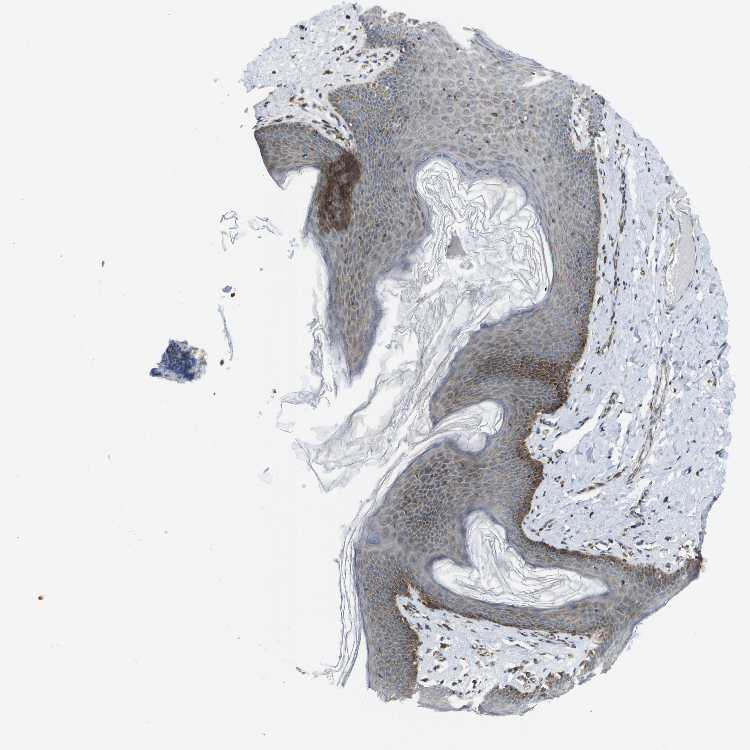

SKIN 1 - Antibody stainingi

Antibody staining in the annotated cell types in the current human tissue is reported as not detected, low, medium, or high, based on conventional immunohistochemistry profiling in selected tissues. This score is based on the combination of the staining intensity and fraction of stained cells.

Each image is clickable and will lead to virtual microscopy that enables deeper exploration of all samples and also displays staining intensity scores, fraction scores and subcellular localization as well as patient and tissue information for each sample.

Antibody HPA017160

Langerhans Low

Fibroblasts Medium

Keratinocytes Low

Melanocytes Low

SKIN 2 - Antibody stainingi

Epidermal cells Medium